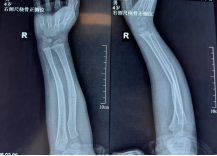

2月9日,4岁的小嘉佑被父亲紧紧抱在怀里来到了西安市红会医院手法复位室,孩子的右前臂明显肿胀、变形。接诊的张晓星医生立即进行体格检查,并安排影像学检查。X线片显示,小嘉佑为典型的儿童尺桡骨双骨折,骨折线横贯前臂中下段,骨折端不仅存在明显的侧方移位,还伴有一定程度的成角畸形。

复位成功后,孩子原本扭曲变形的前臂也恢复了正常轮廓。团队为患儿采用超腕超肘石膏托进行外固定。这种特殊固定方式既能有效维持复位后的位置、防止再移位,又能通过精准塑形贴合前臂生理弧度,为骨折愈合提供稳定而舒适的环境。复位后即刻复查的X线片正位片显示,桡骨与尺骨骨折端对位良好,侧方移位完全纠正;侧位片显示掌背侧成角畸形已有效矫正,力线接近正常。“对于4岁的儿童而言,这样的复位效果已非常理想。”董博主任向家属耐心解释道,“儿童骨骼具有远超成人的塑形能力,即使存在轻微对位不良或小角度成角,在后续生长发育过程中也能自行重塑。因此,临床并不要求绝对解剖复位,而是在保障功能恢复的前提下,尽可能减少创伤。”